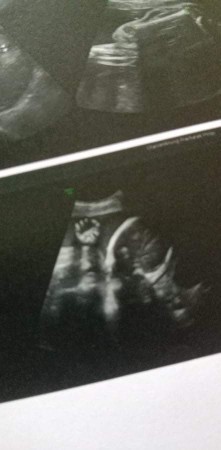

32weekเพศหญิงค่ะเเต่ไม่หันหน้าให้เห็นสักรอบ